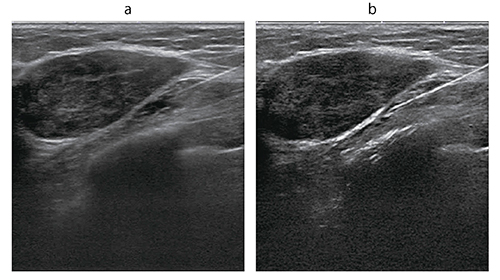

穿刺吸引細胞診(FNA)に当たり,演者は通常の採血などで用いられる太さの22Gの穿刺針を使用することが多いが,コアバイオプシーでは16Gや14Gの針が,さらにマンモトームでは11G,あるいは8Gという非常に太い針が使用される。針が太いほど多くの組織を採取でき,十分な診断能が得られるが,患者の侵襲は大きくなり,血腫などの合併症のリスクが大きくなることを考えると,針が太ければ良いとは一概には言えない。また,超音波ガイド下では,太い針は明瞭に描出されるものの,細い針は不明瞭となる。特に,最近の超音波はビームの収束が強く,フォーカスが針にきちんと合わないと明瞭に描出されないというケースもよく経験される。

細い22G穿刺針によるFNAにより,患者の負担を抑えながら診断できる例は少なくない。しかし,ガイドとなる超音波画像で針が描出できなければ,施行そのものが困難となる。そこで現在,東芝メディカルシステムズが開発した針強調法を用いた検討を行っている(図8)。実際に,線維腺腫症例に対し,腫瘍の真下に麻酔目的に22G針を穿刺したところ,通常のBモードでは針が不明瞭であるが(図9a),針強調法では鮮明に描出された(図9b)。

将来的に,この新しい技術が導入されることによって,細胞針や針生検が容易に施行できるようになり,患者の負担軽減につながることが期待される。

図8 針強調法の概要(W.I.P.)

図9 22G穿刺針で穿刺中のBモード画像(a)と針強調画像(b)